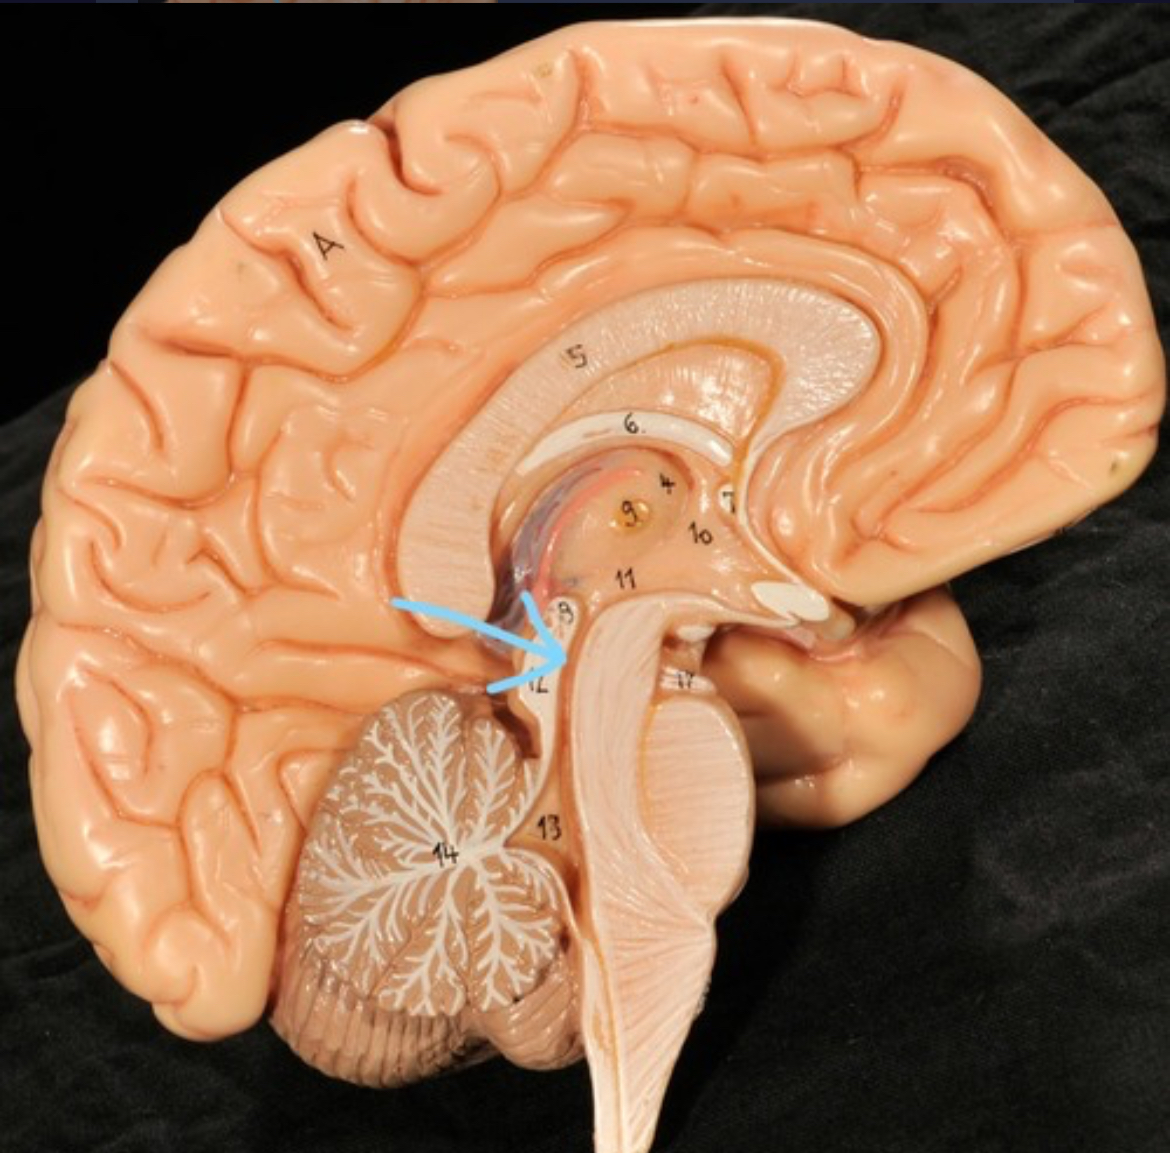

Brain stem

Pons

Medulla oblongata

Choroid plexus of 3rd ventricle

Cerebral aqueduct (midrain)

4th ventricle

central canal